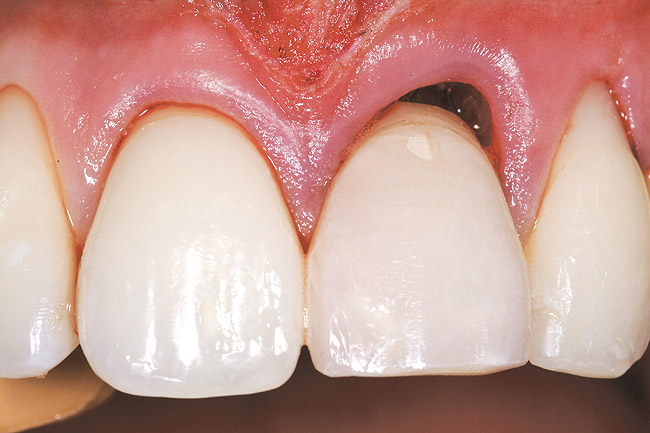

Creation of the facial pouch was accomplished as outlined earlier. Intrasulcular incisions were made from the distal line angle of the right central incisor to the distal line angle of the left canine, with care given to not totally incise the papillae at the interproximal aspect. Using mucoperiosteal elevators and blunt dissection, the pouch was extended apically beyond the mucogingival junction, and laterally to the facial aspect of the tunneled papillae. The pouch was then deepened and mobilized by sharp supraperiosteal dissection. The pre-trimmed acellular dermal matrix (AlloDerm) rehydrated with non-activated PRP, was then placed into the pouch superior to the allogenic bone graft placed to correct the facial defect at the implant site, from the mesial of the right central to the mesial of the left canine (Figure 27). The acellular dermal matrix was then secured with 6.0 polypropylene sutures, and the pouch coronally advanced to cover the dermal matrix graft completely, using 5.0 monocryl sutures by an interrupted sling suturing technique (Figure 28).

The provisional restoration was an immediate non-functional restoration, and was free of contact in centric occlusion, protrusive, and right and left lateral excursive movements. Figure 29 is the 6-week postoperative view. Note the free gingival margin at the mid-facial point of the left central incisor, and compare that to the pretreatment level seen in Figure 21. The site would be allowed to heal and mature for an additional 6 weeks prior to completion of the final implant-supported restoration.

Figure 28  Case Three Pouch coronally advanced over the dermal matrix graft.

Figure 28

Figure 29  Case Three 3-month postoperative tissue emergence profiles..

Figure 29